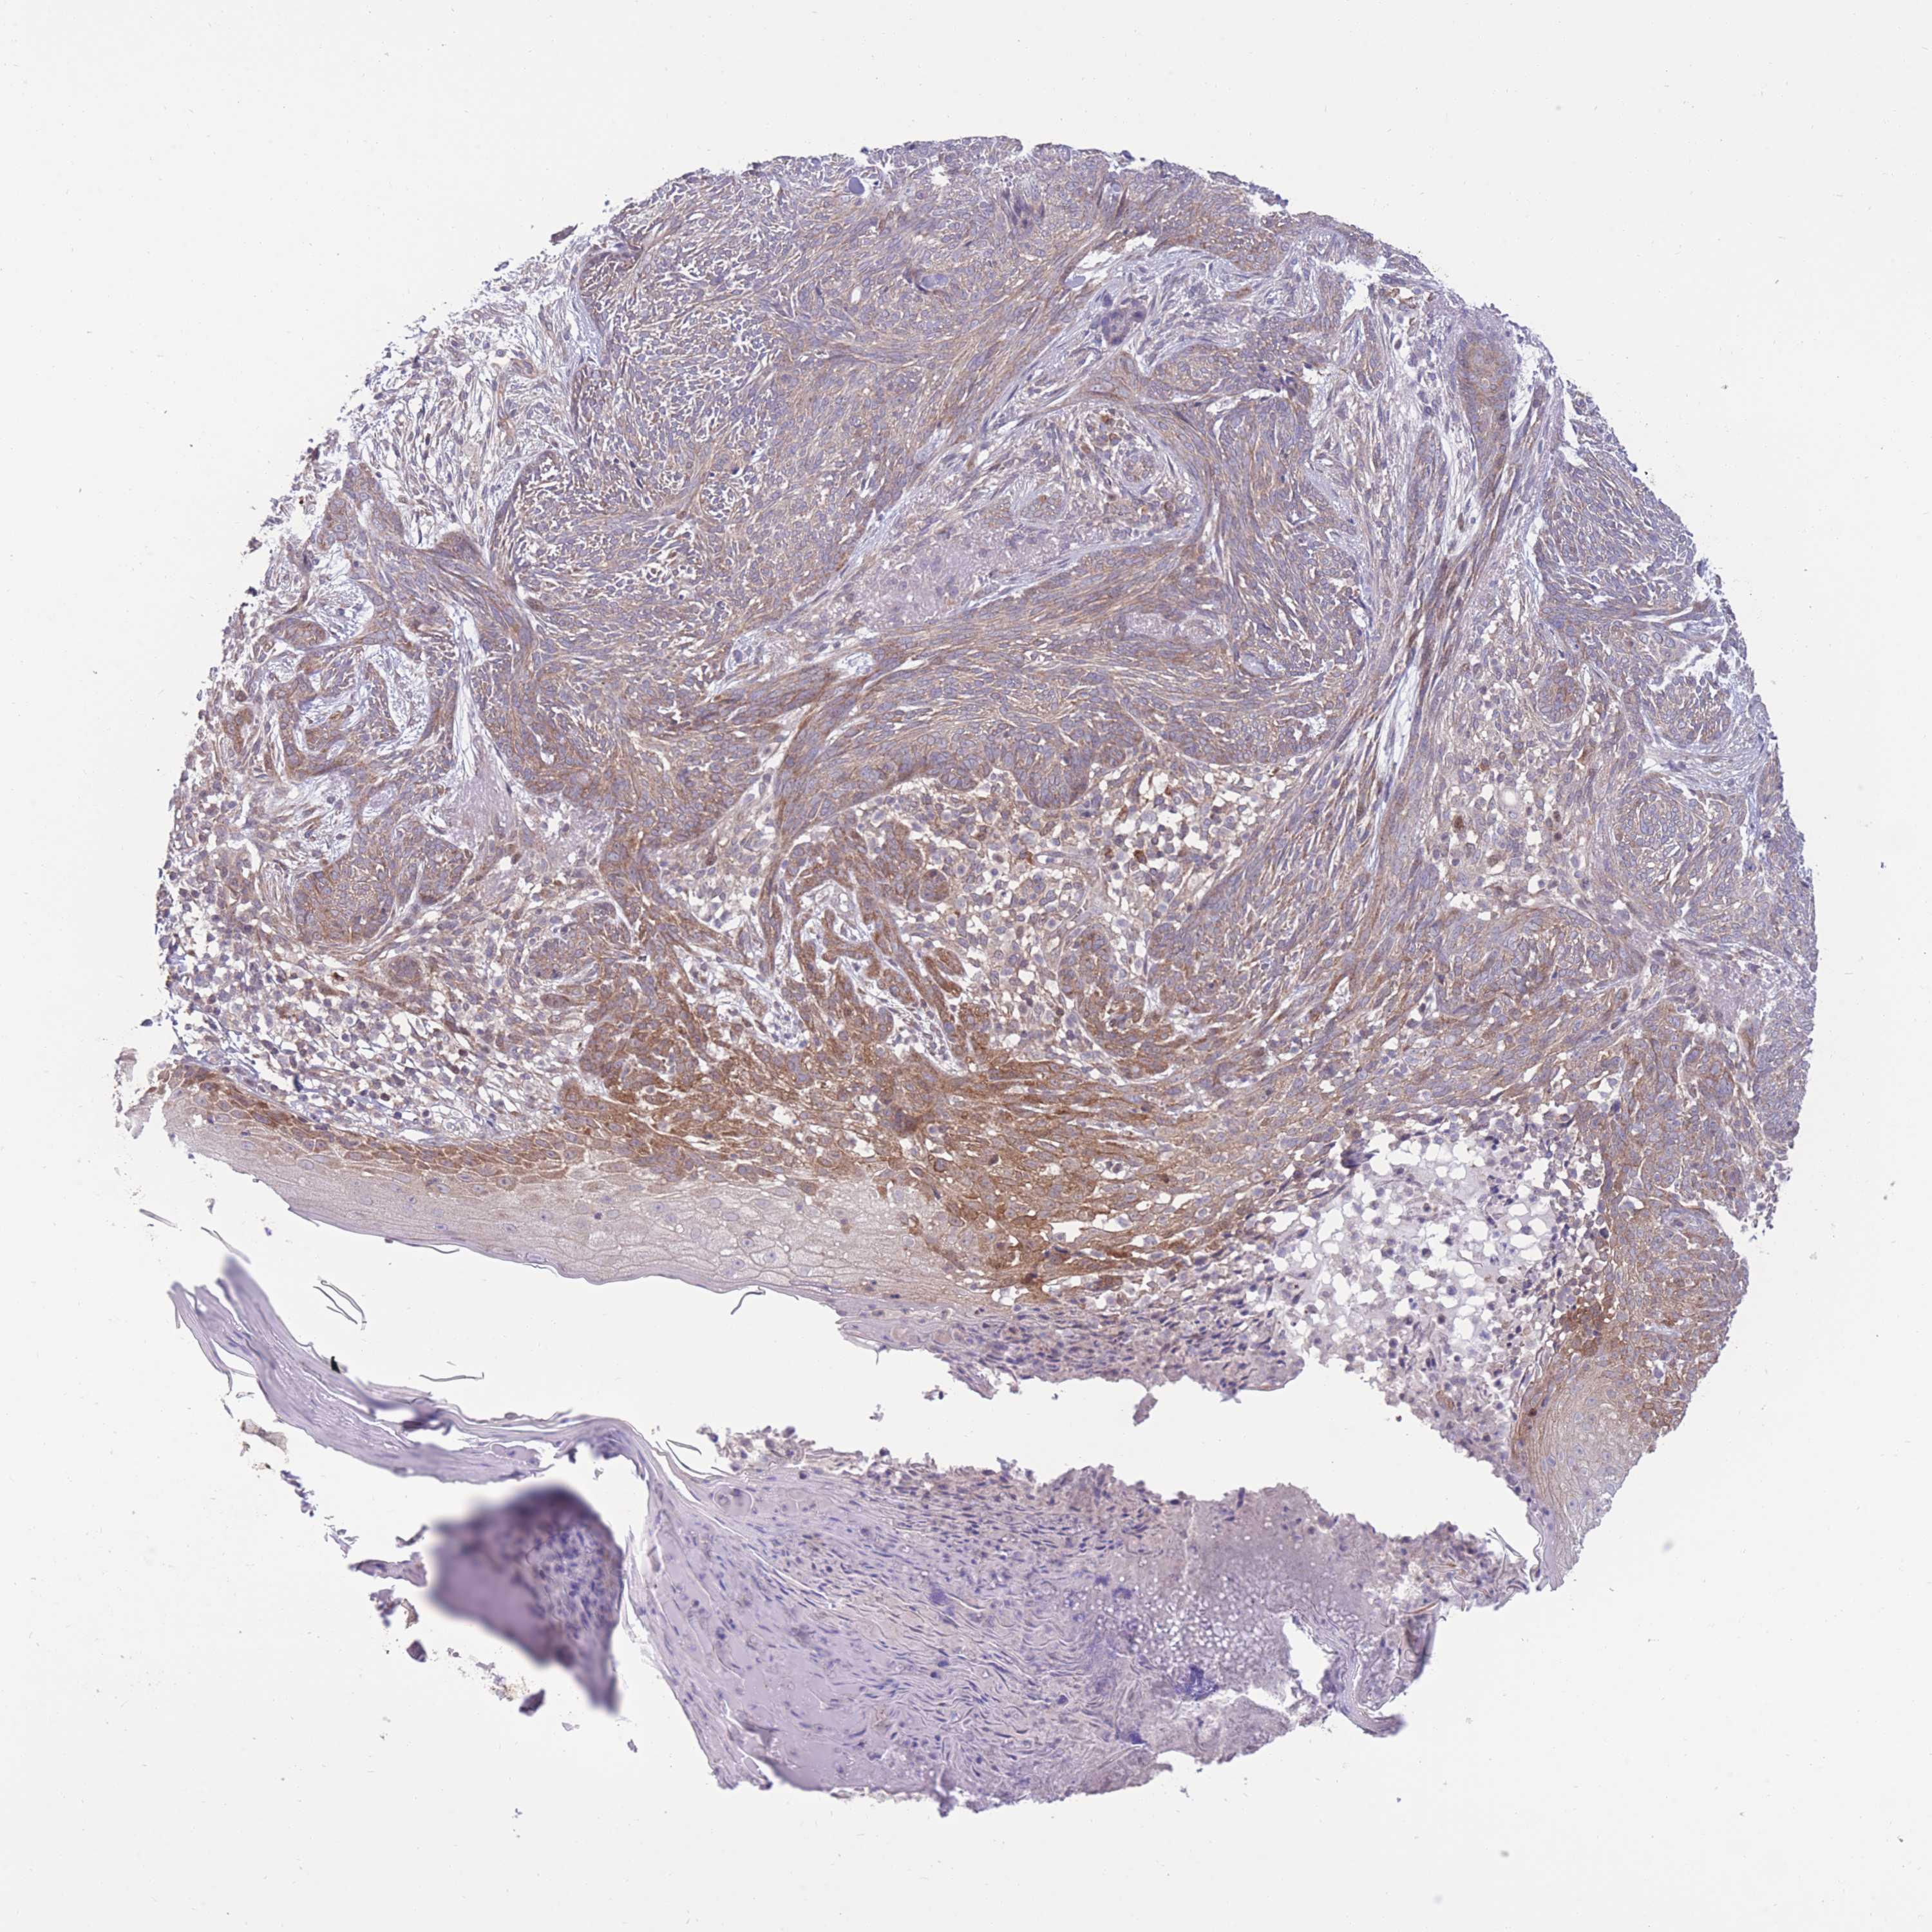

SKIN CANCER - Protein expressioni

A mouse-over function shows sample information and annotation data. Click on an image to view it in a full screen mode. Samples can be filtered based on level of antibody staining by selecting one or several of the following categories: high, medium, low and not detected. The assay and annotation is described here.

Antibody staining in the annotated cell types in the current human tissue is reported as not detected, low, medium, or high, based on conventional immunohistochemistry profiling in selected tissues. This score is based on the combination of the staining intensity and fraction of stained cells.

Each image is clickable and will lead to virtual microscopy that enables deeper exploration of all samples and also displays staining intensity scores, fraction scores and subcellular localization as well as patient and tissue information for each sample.

Antibody CAB046012

Squamous cell carcinoma, NOS